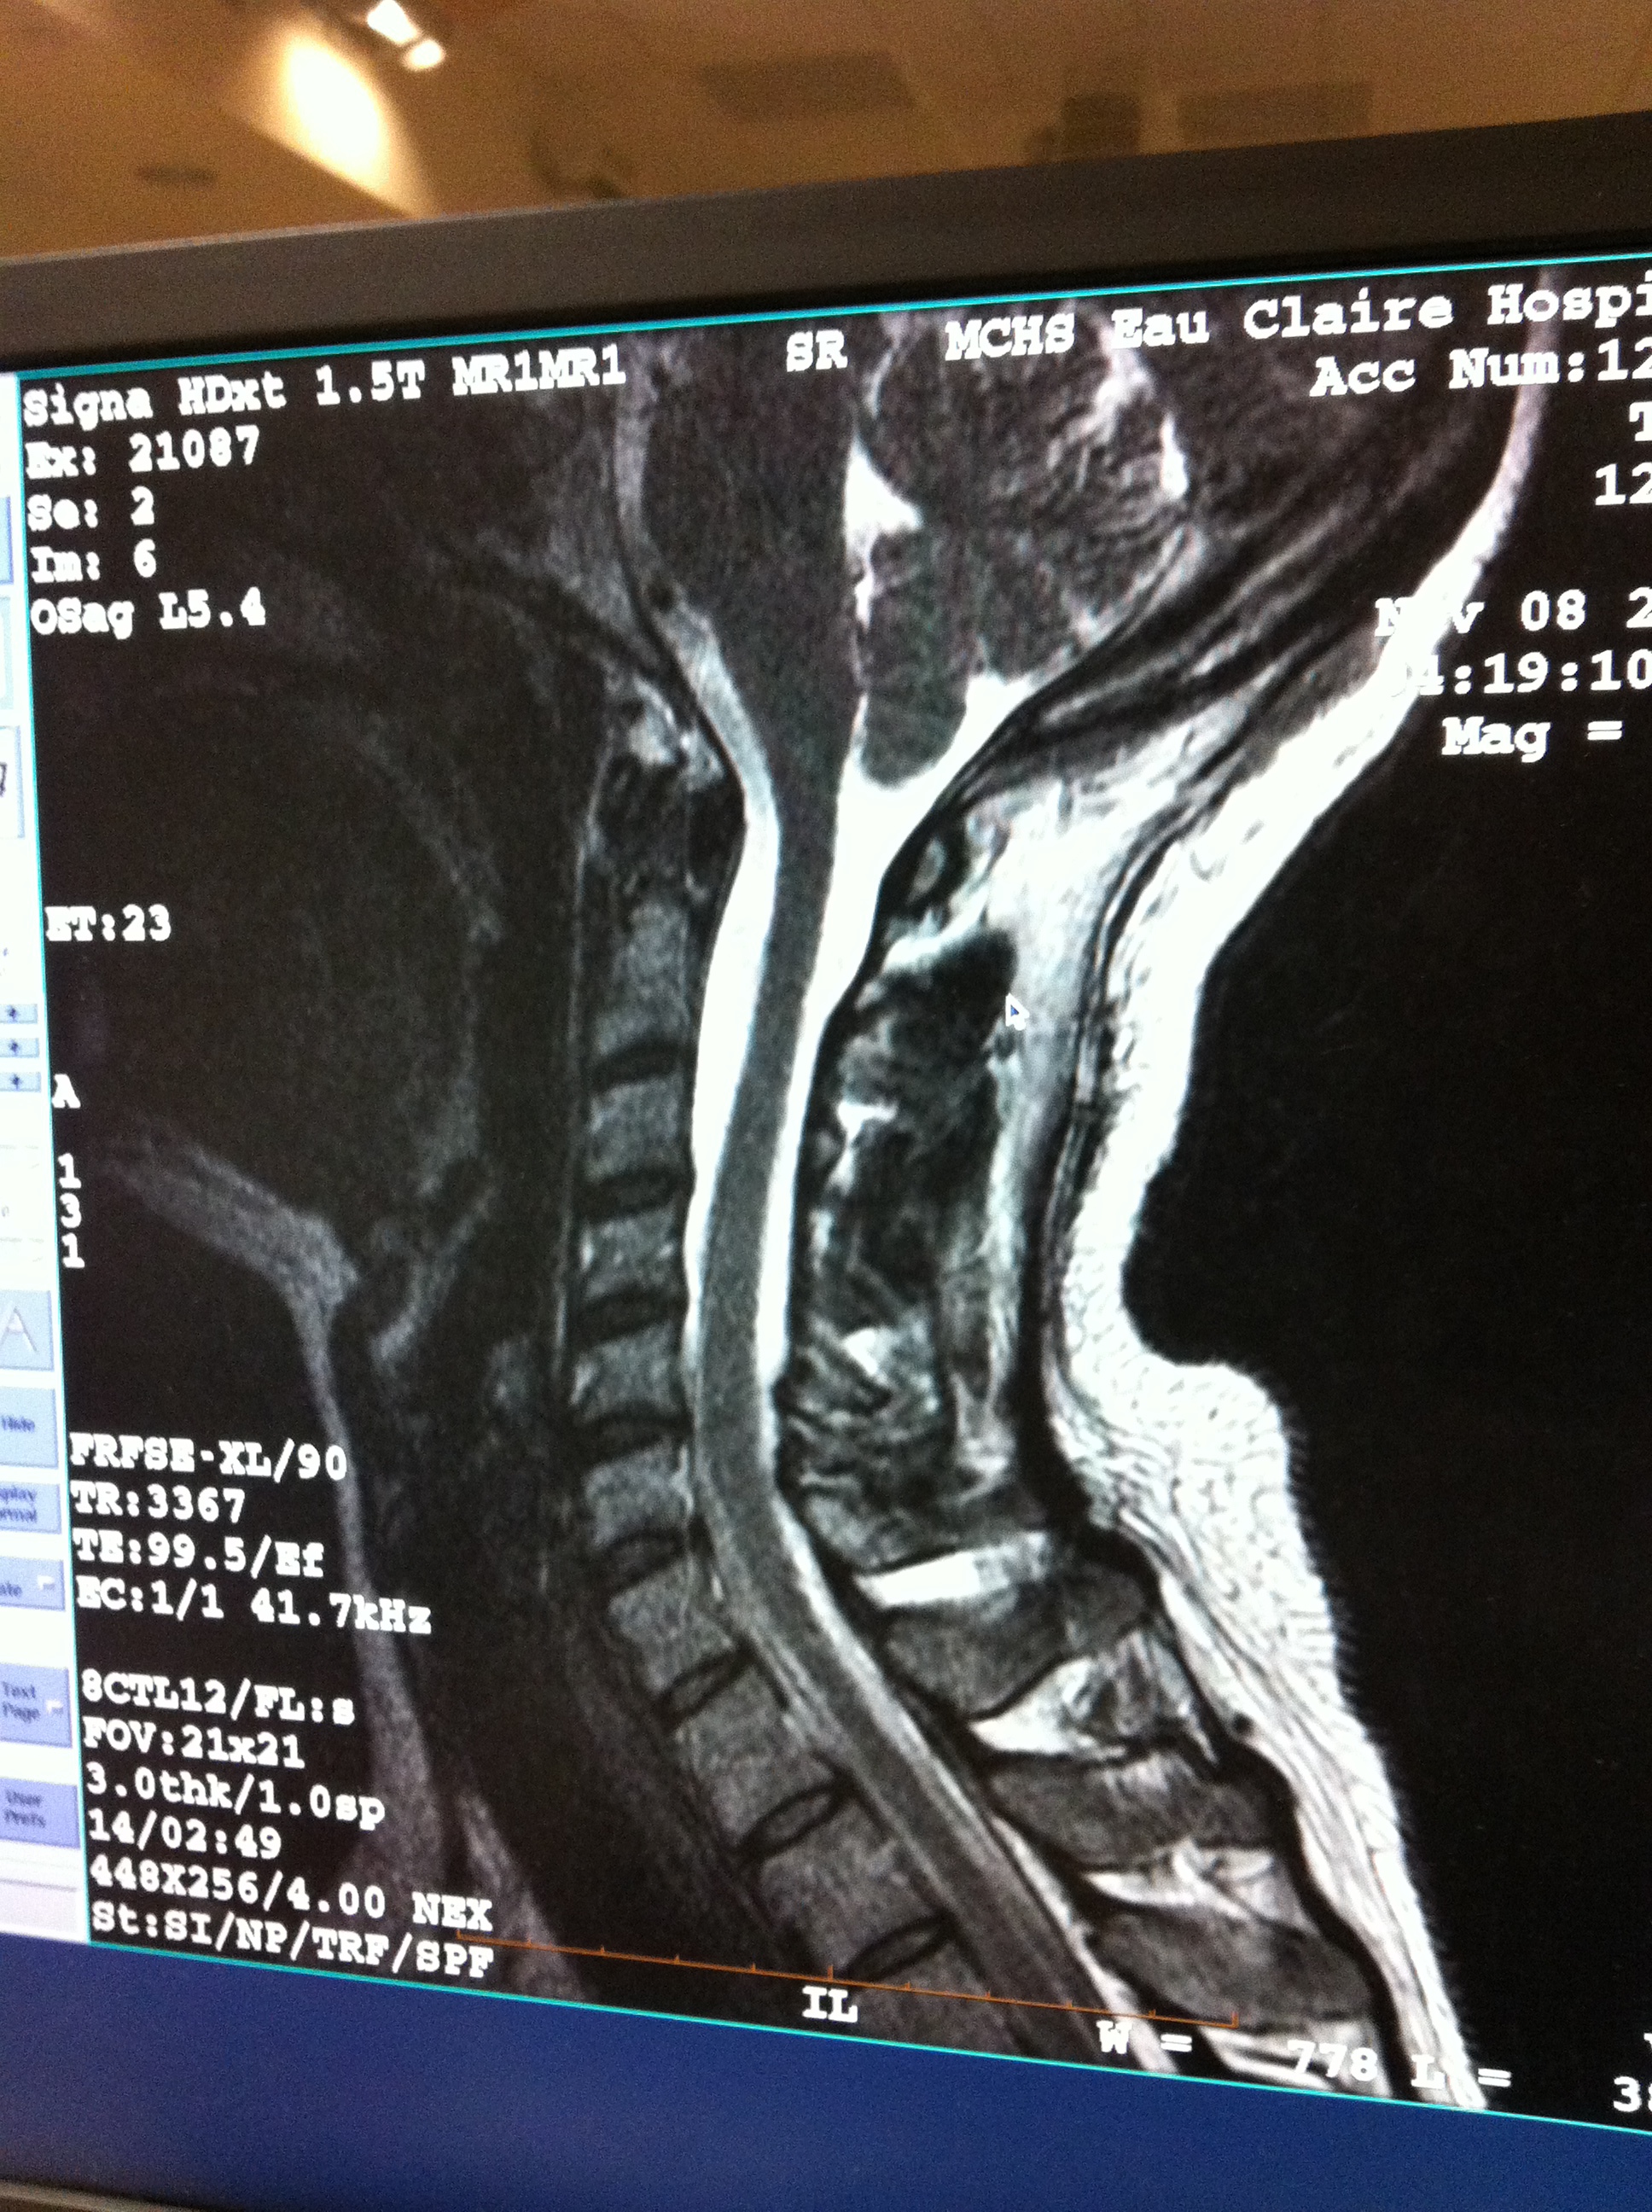

Looking for opinions on my scan - does everyone think this looks like chiari???

you definately have some herniation but it looks like there is plenty of fluid there. You also seem to have a slight cervical stenosis at c5 posteriorly and cervical lordosis ... combined they could be altering the CSF flow. I would get a disk of the MR to take to the appointment and have the neurologist look at the parasaggital and coronal slides of the tonsils to check for asymmetry ... check out this lecture entitled "Chiari Malformation: A Name Which Leads to Unnecessary Confusion" at this link. By his standards, you would definately have "Hindbrain Herniation" http://www.csfinfo.org/node/307 good luck

You cannot really tell if there is CSF blockage without a cine-flow MRI - the image you have is a T2 mid-saggital image from your run of the mill MRI ... by plenty of fluid, I mean fluid behind the cerebellar tonsil which, as a layman, would make me think that there is some flow but it may be altered because there does appear to be some tonsilar descent which could cause your symptoms (a point of debate by neurologists). Ideally, you would also want to see some more fluid underneath the bottom of your cerebellum as well. However, your cerebellum appears to be resting on the skull base when it should kind of float. Dr. Rekate speaks about the effects of altered flow in the video that I suggested. It is the crux of his arguement for establishing diagnostic criteria for Chiari Malformation. A NS who does not specialize in Chiari probably holds the opinion that if there is flow at all, the herniation, regardless of length, is "incidental" - meaning not the cause of your problems. I personally was told that by the first neurosurgeon that I saw - at Yale. I spent most of the nest year in a dark, quiet room - alone with raging headaches and shooting neck pain (that was year two). He was wrong. Second, your scan does not show markedly "pointed" tonsils. This would be strike two by the mis-diagnosis umpire (the radiologist). Strike three is the fact that the herniation does not extend down to c1 - your first cervical vertebrae. You appear to have a large foramen magnum (hole in the bottom of your skull) which most people with Chiari have (ironically ... since the decompression surgery makes that hole even bigger). Hence, your tonsils are not being disfigured (made pointed) but they may still be disrupting the flow of CSF though not obliterating it. (again, see video) So, a quick glance by a radiologist who does not know much about Chiari might cause him or her to not even measure the descent of the cerebellar tonsils because there is fluid in back of the tonsils, it does not extend to c1, and it does not appear pointed on the mid-saggital image that appears here. Thus, I cannot encourage you enough to get the CD of your scan before your appointment and if there is no mention of herniation on the radiologist report, ask your NL to take a look at it and measure the herniation - especially the views that I mentioned in my last response. I hope that this helps. Good luck!

That does appear to be a chiari to me